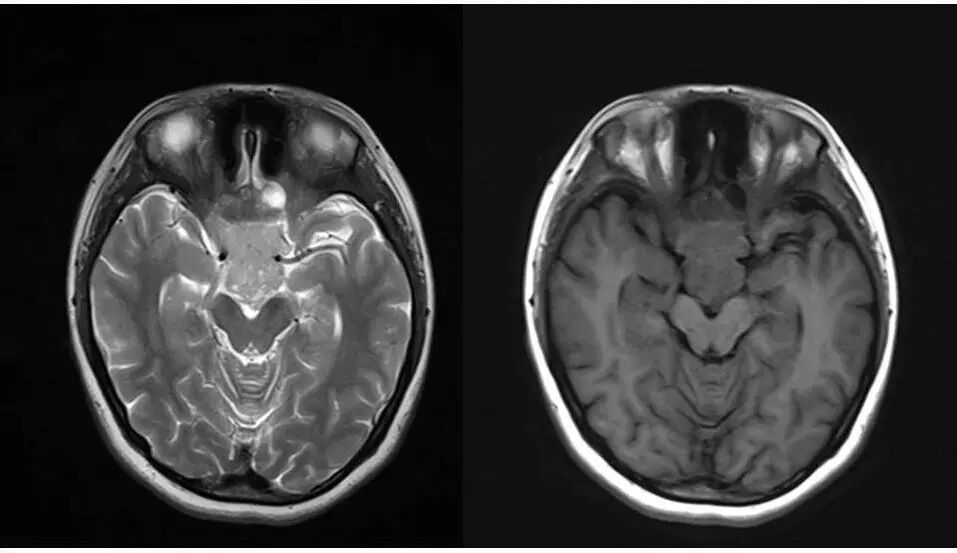

2.MR检查显示肿瘤位于鞍区,分叶状生长,呈稍长T2、稍长T1异常信号影,边界清楚,内部信号不均匀,其内可见“微囊”状异常信号影,视交叉受压上抬,DWI呈等或略高信号影,注药后呈不均匀明显强化;

5.影像表现确定肿瘤源于垂体,部位、信号、生长方式、内部结构、骨质破坏,增强显示等均符合垂体瘤诊断。